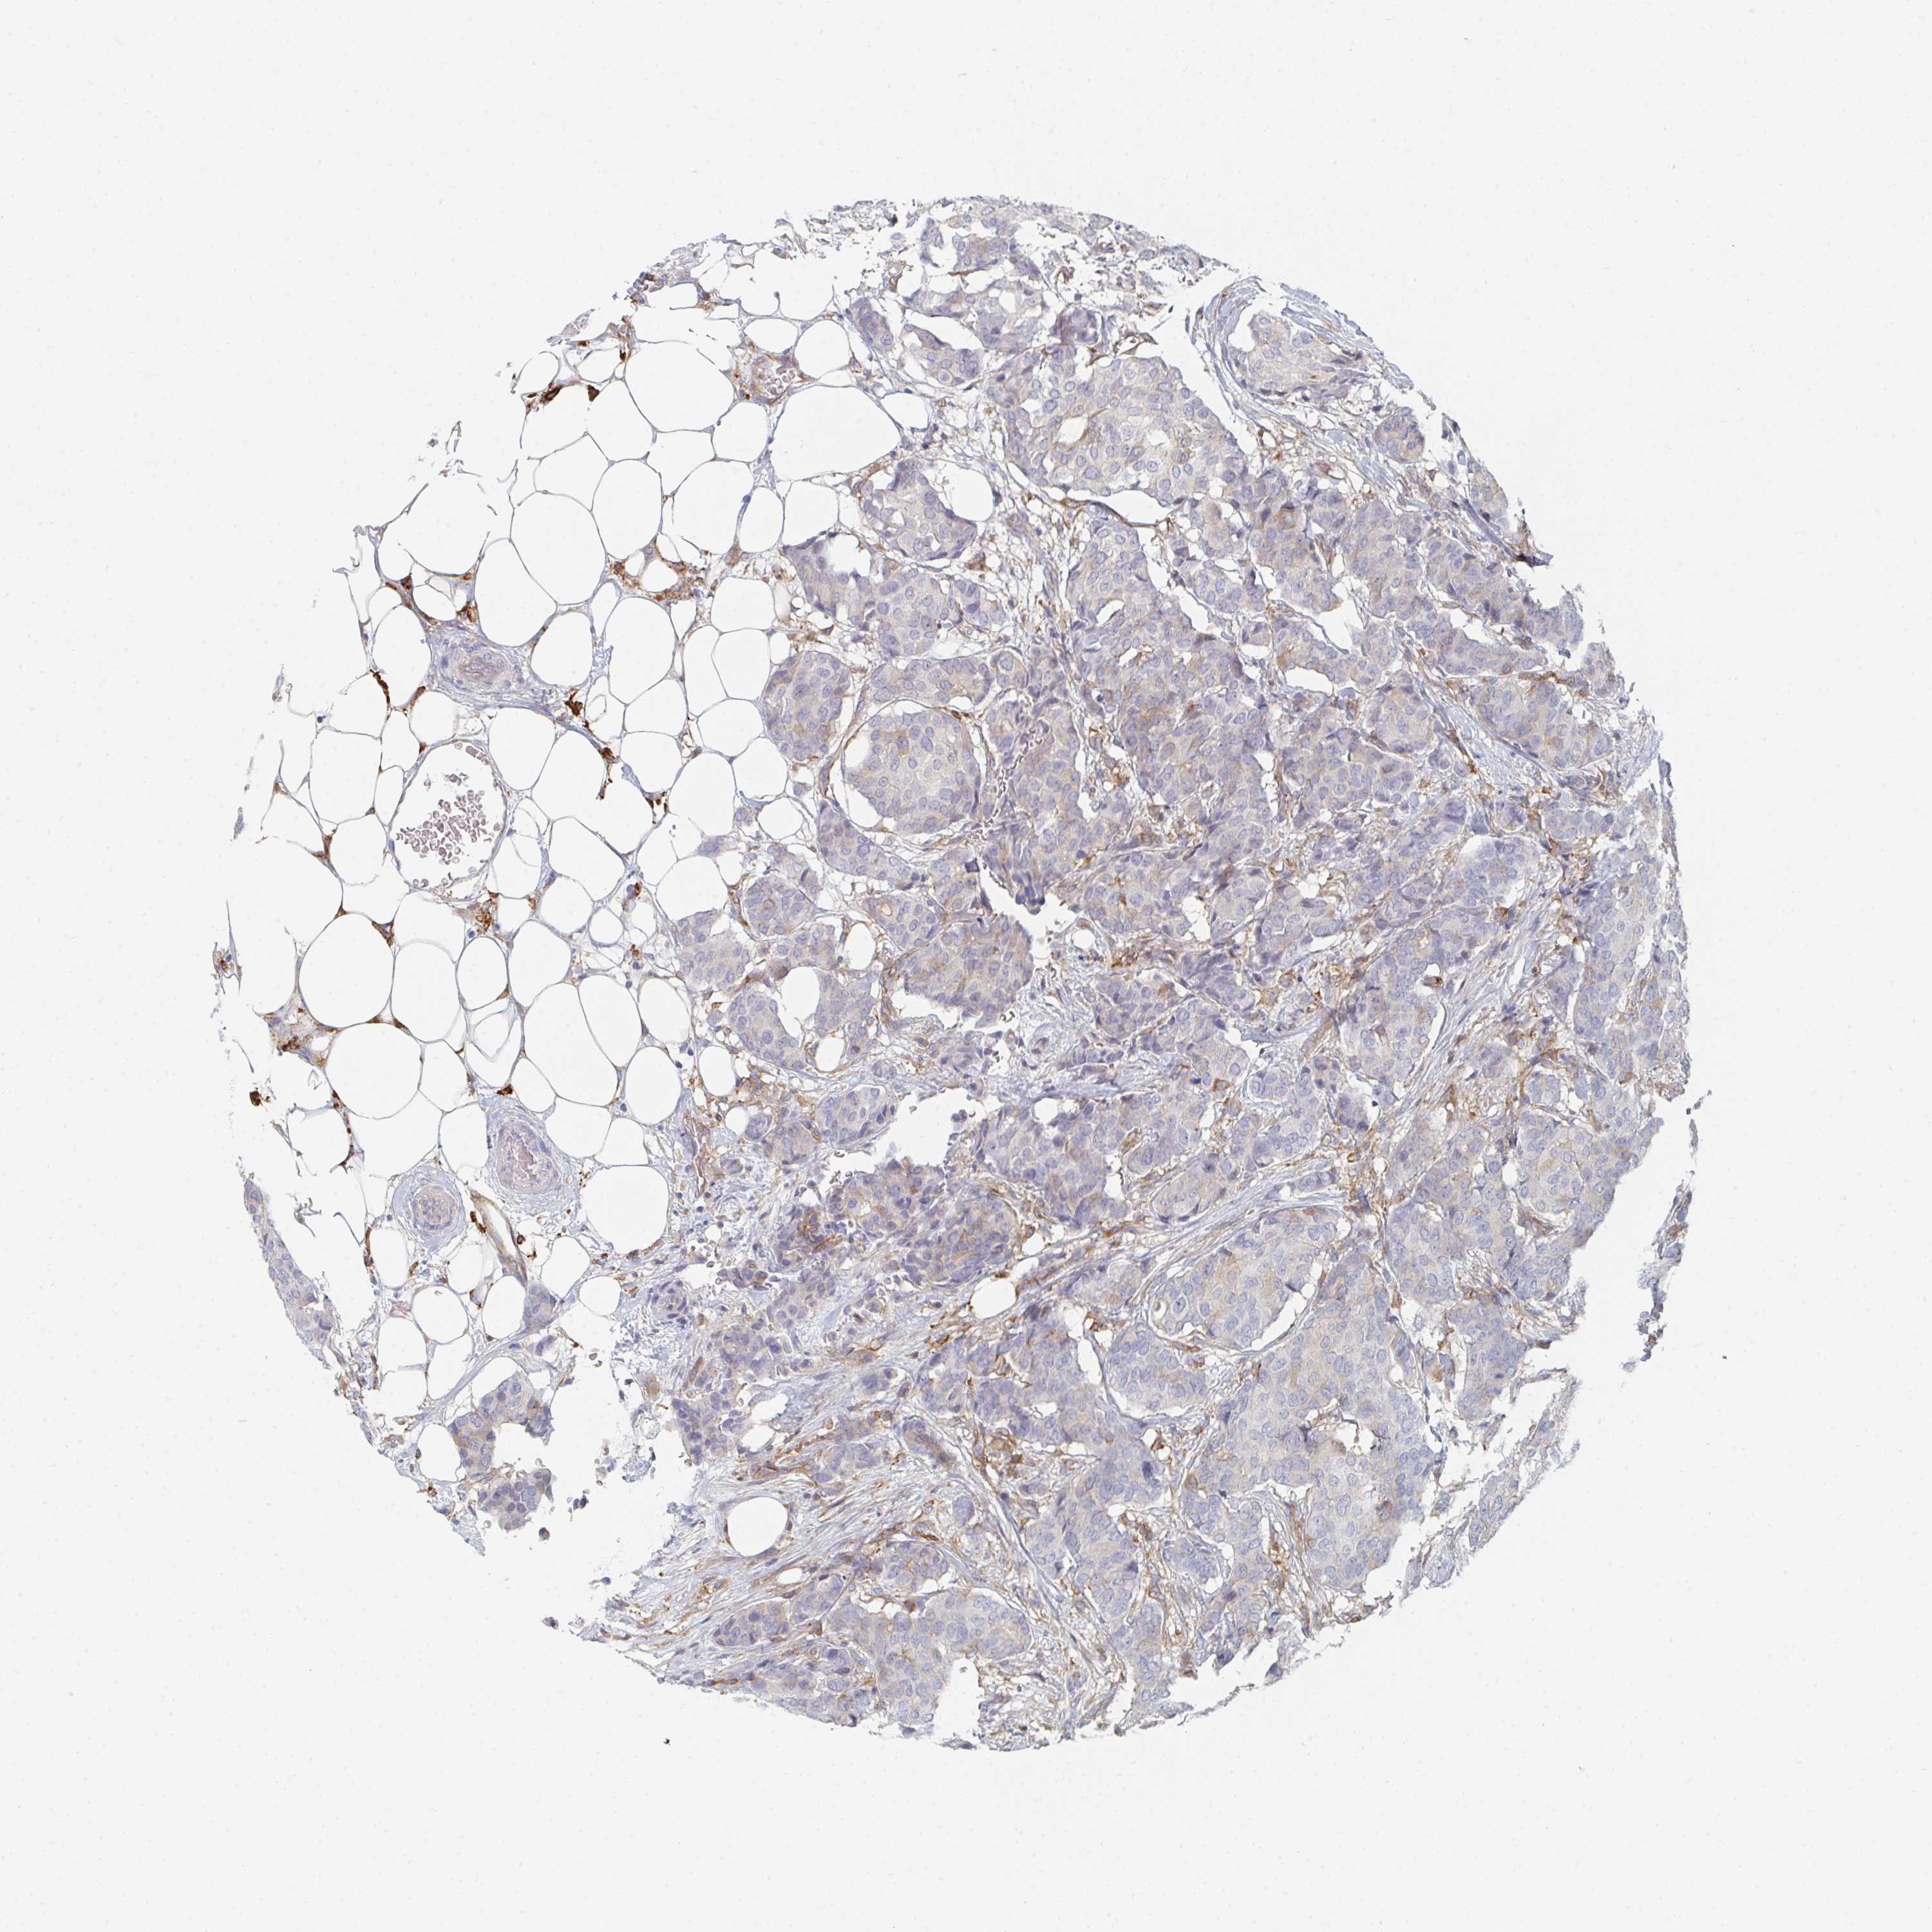

CANCER BREAST CANCER Show tissue menu

BRCA TCGA BRCA VALIDATION PROTEIN EXPRESSION